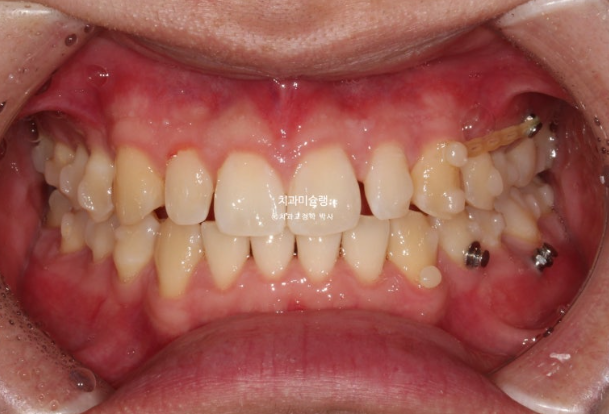

11개 추가장치를 모두 낀 후 25년 6월 치료를 마무리 합니다.

이제 왜소치 무삭제 라미네이트가 들어갈 차례 입니다.

왜소치 라미네이트는 주변치아 색깔에 어울리도록 맞추는 것이 좋습니다.

자연스럽게 잘 치료가 되었습니다.

총 치료기간은 2년 6개월 재제작은 2회 했습니다.

어금니 교합은 좋고 1급 교합관계를 보입니다.

거미스마일과 중심선이 개선이 되었습니다.

깔끔하고 정돈된 미소가 돋보입니다.